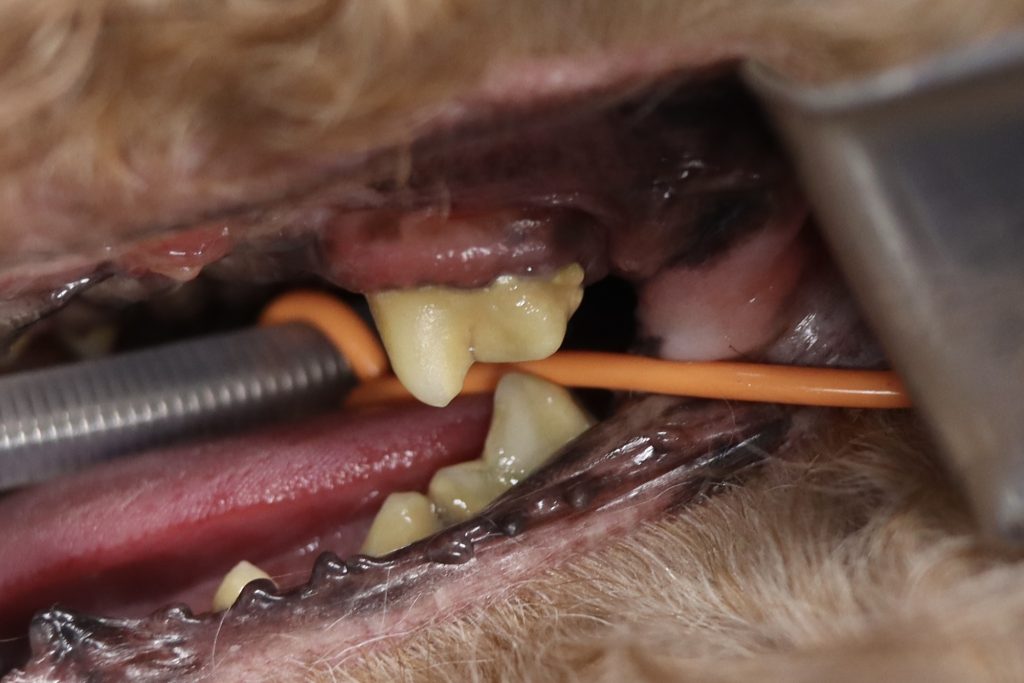

次に下の写真を見てみましょう。

先ほどの症例に比べると同じ場所に分厚い歯石が沈着し、歯全体を覆っています。

歯科レントゲンを撮ってみると歯を支える歯槽骨が重度に融解しており、重度歯周炎と診断しました。

また、歯槽骨の融解は鼻まで達しており、口腔鼻腔瘻を塞ぐ粘膜フラップ手術も必要となりました。

そのため、抜歯を実施しましたが、麻酔処置は2時間半にも及びました。